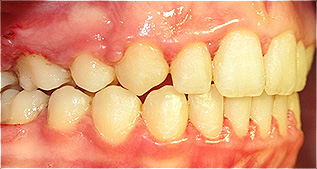

Após dois anos de tratamento ortodôntico.

![]() |